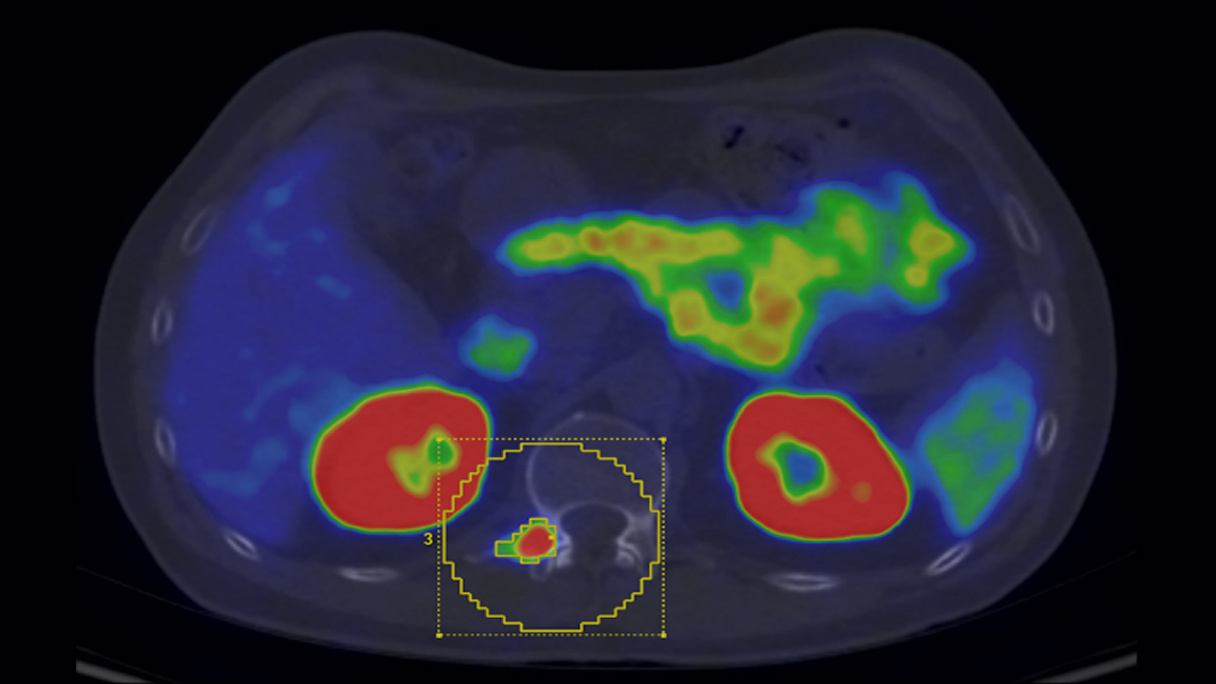

There is a world outside the stent mesh

Caso condiviso da Saima Mushtaq

Paziente con anamnesi di malattia coronarica e pregresso impianto di stent sulla discendente anteriore sinistra.